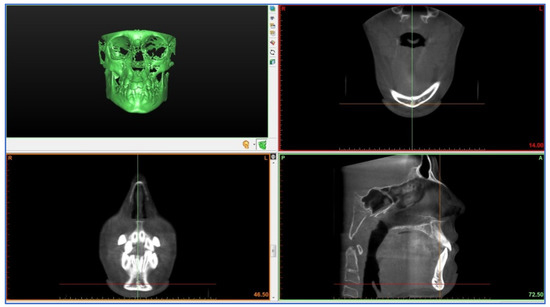

2. Materials and Methods